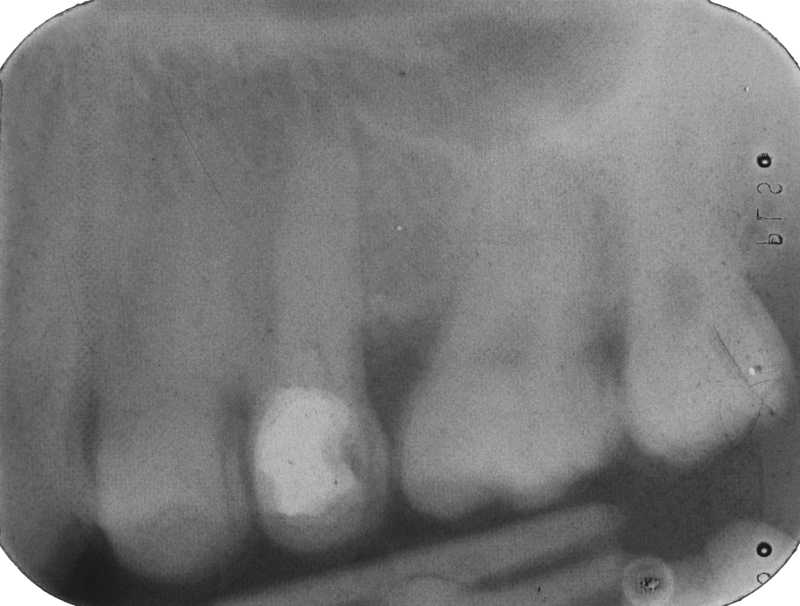

Dental Radiography Film Faults. Quiz 1

Dental Radiography Film Faults. Quiz 1 Enhanced Dental CPD Online Dental Radiograph Quiz test your knowledge of the history and advancements in dental radiography! test your dental radiograph knowledge! discover the improvements in exposure time and film quality, and see how far we've come in capturing accurate dental images. quiz yourself with questions and answers for dental radiology practice test, so you can be ready for test day. . Dental Radiograph Quiz.